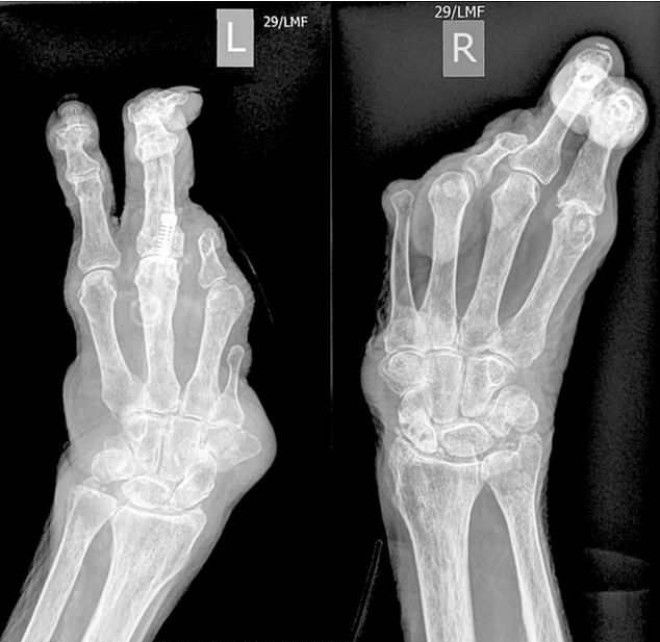

94-летняя жительница графства Восточный Суссекс, Британия, наповал сразила врачей. Она поступила в больницу с подозрением на инфекцию мочевых путей и шокировала медиков своими ногами-клешнями и такими же руками (эктродактилия). Бабушка рассказала, что несмотря на врожденный порок, она всю жизнь справлялась без посторонней помощи, воспитала сына и вяжет для своей семьи.